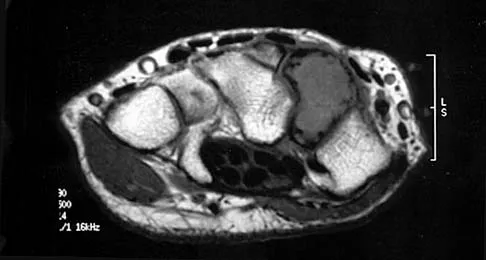

Question 92

Figure 30 shows the MRI scan of a 68-year-old woman who has left hip pain. What is the most appropriate treatment?